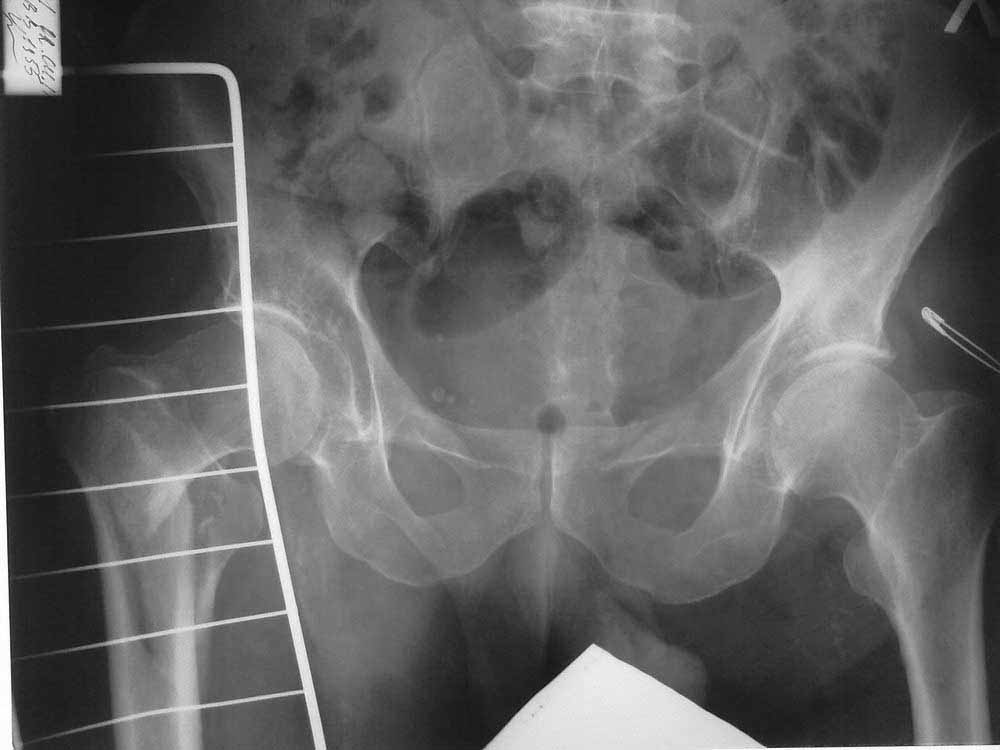

Уважаемые коллеги! Подскажите тактику ведения больного с чрезвертельным перелом.

Больной 56 лет. Травма в быту, упал на правое бедро. Доставлен по линии скорой помощи. Правая нижняя конечность ротирована кнаружи, укорочение на 4 см. Резкая боль в области правого ТБС.

В анамнезе инсульт от 04.2010 г, повторный инсульт 28.02.2011 г. DS:Хроbrническая дисциркуляторная энцефалопатия II ст., последствия ОНМК в виде выраженного спастического гемипареза справа.

Раньше больной передвигался с опорой на правую нижнюю конечность, но активных движений в ноге не было.

Сейчас на скелетном вытяжении, с грузом 8 кг, за бугристость большеберцовой кости.